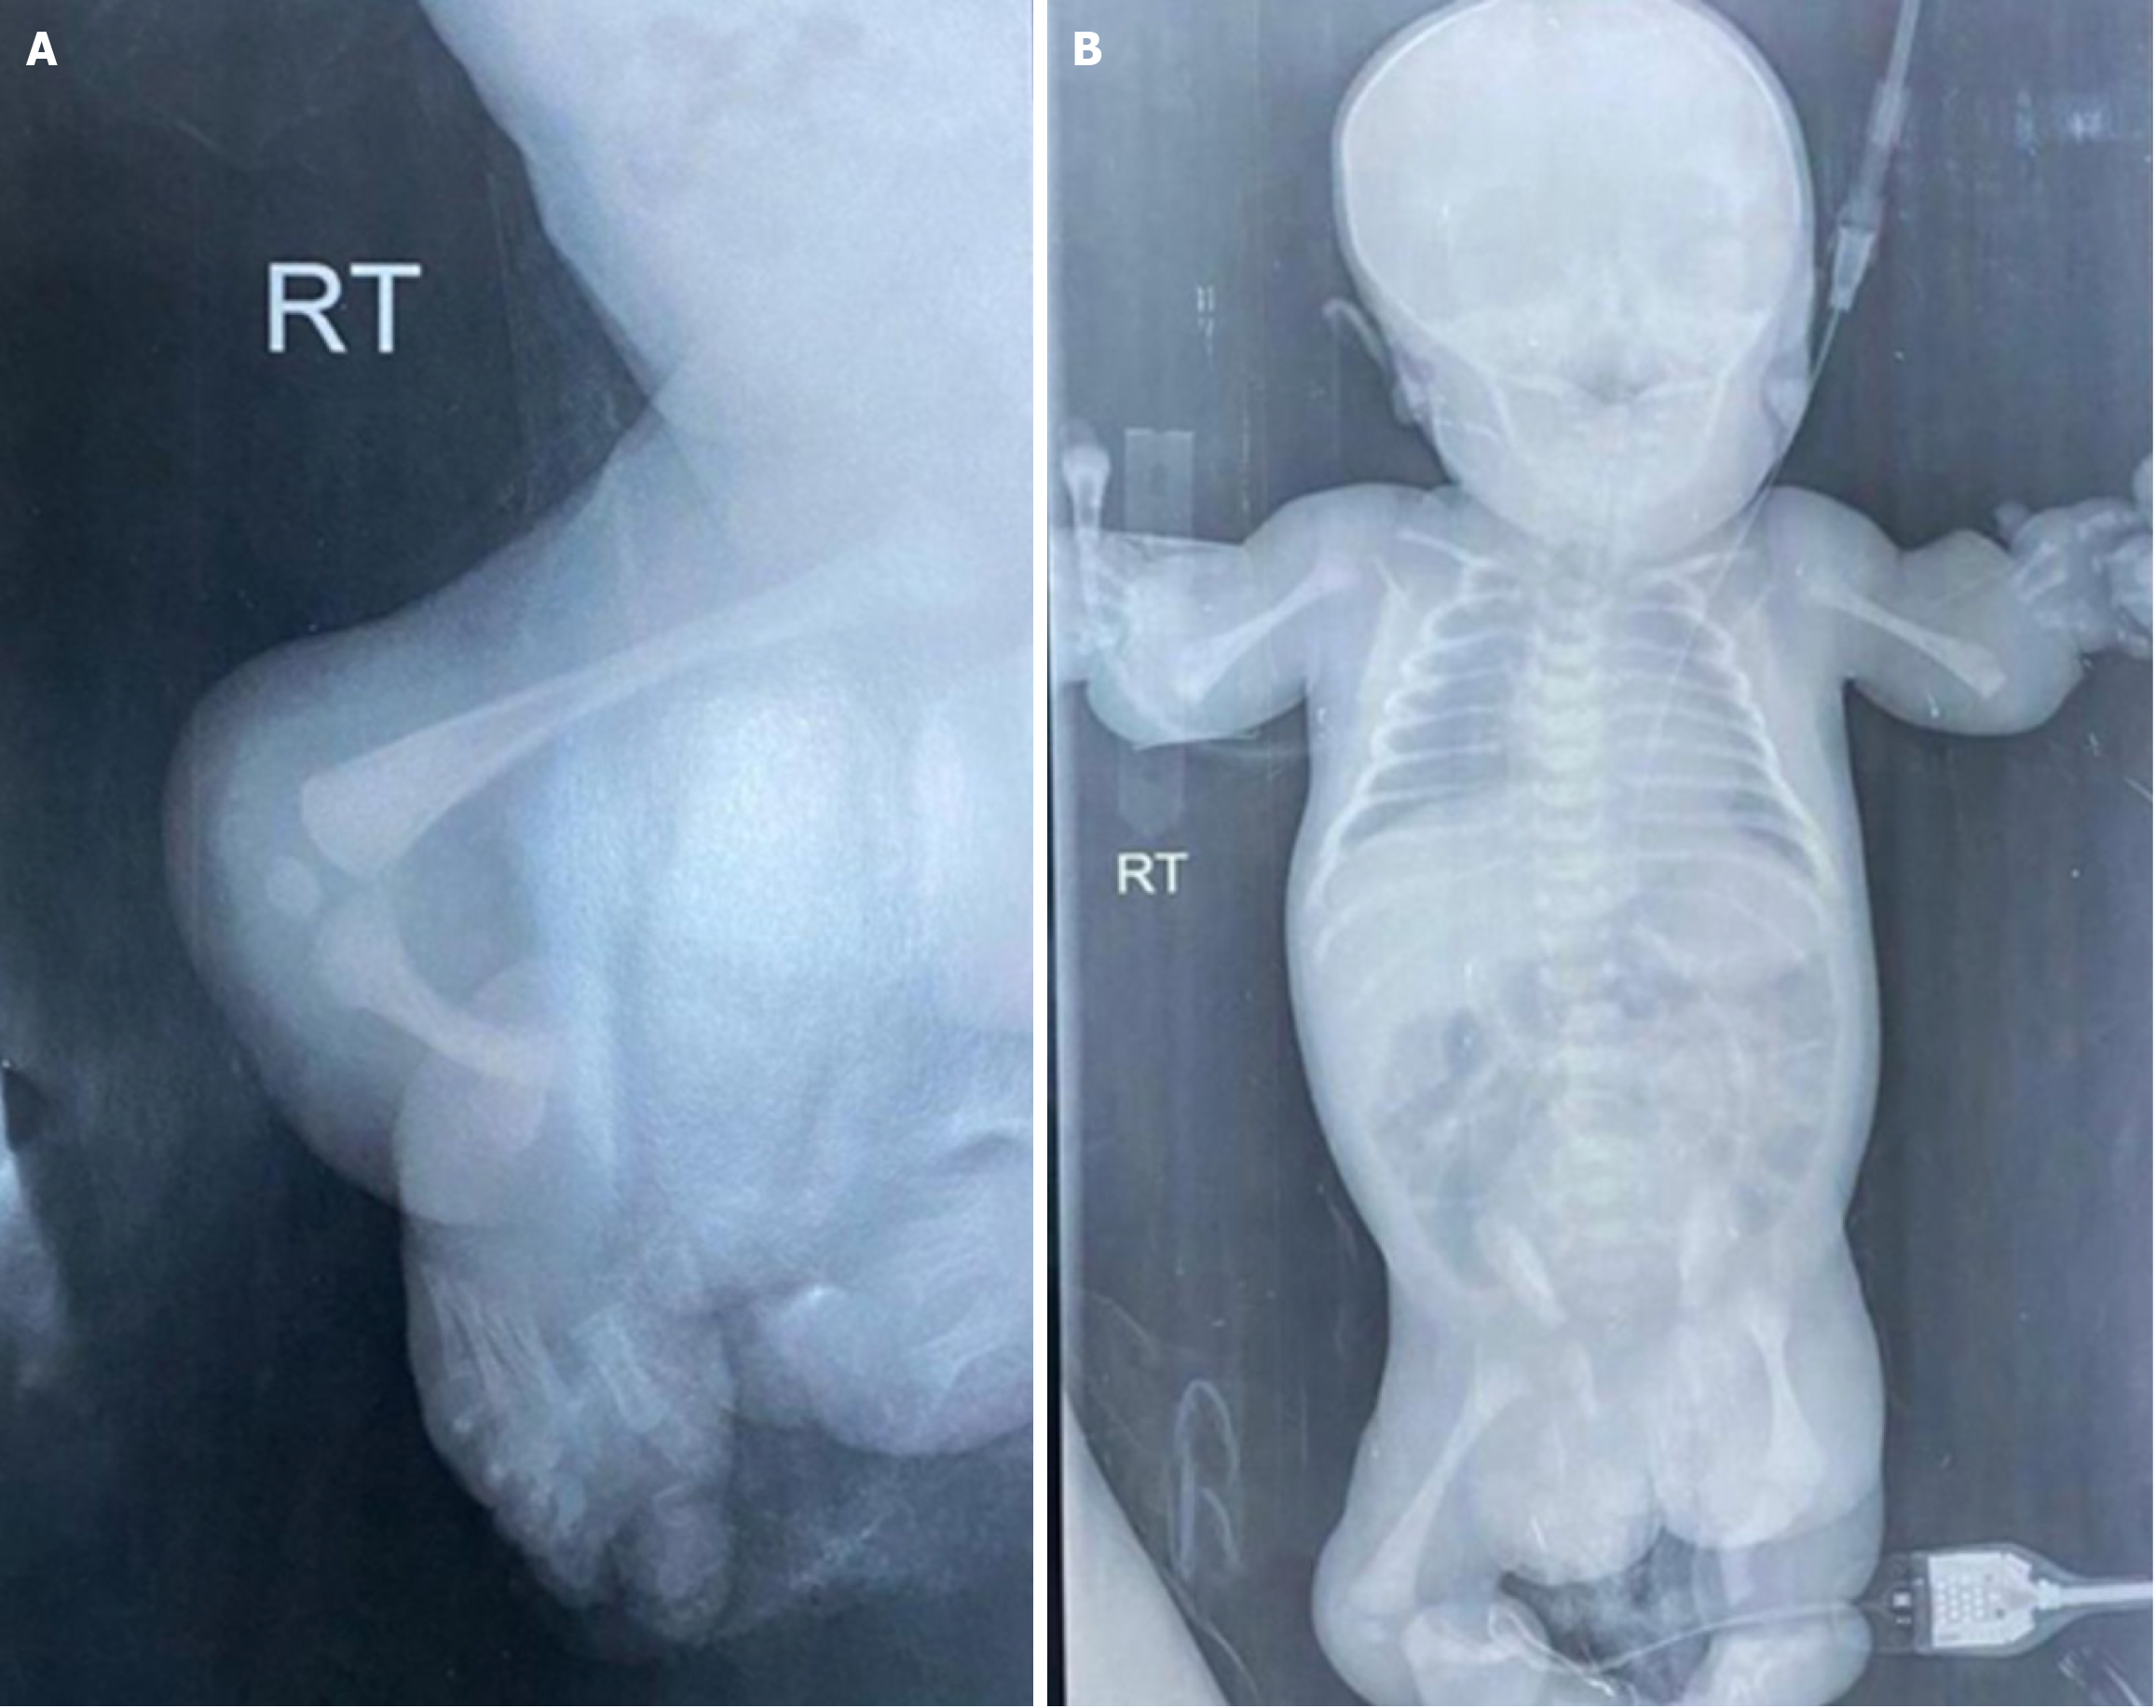

Figure 4 Radiographic findings of bony abnormalities in Roberts syndrome.

A: Right lower limb radiographic findings; B: Whole body bone survey. RT: Right.